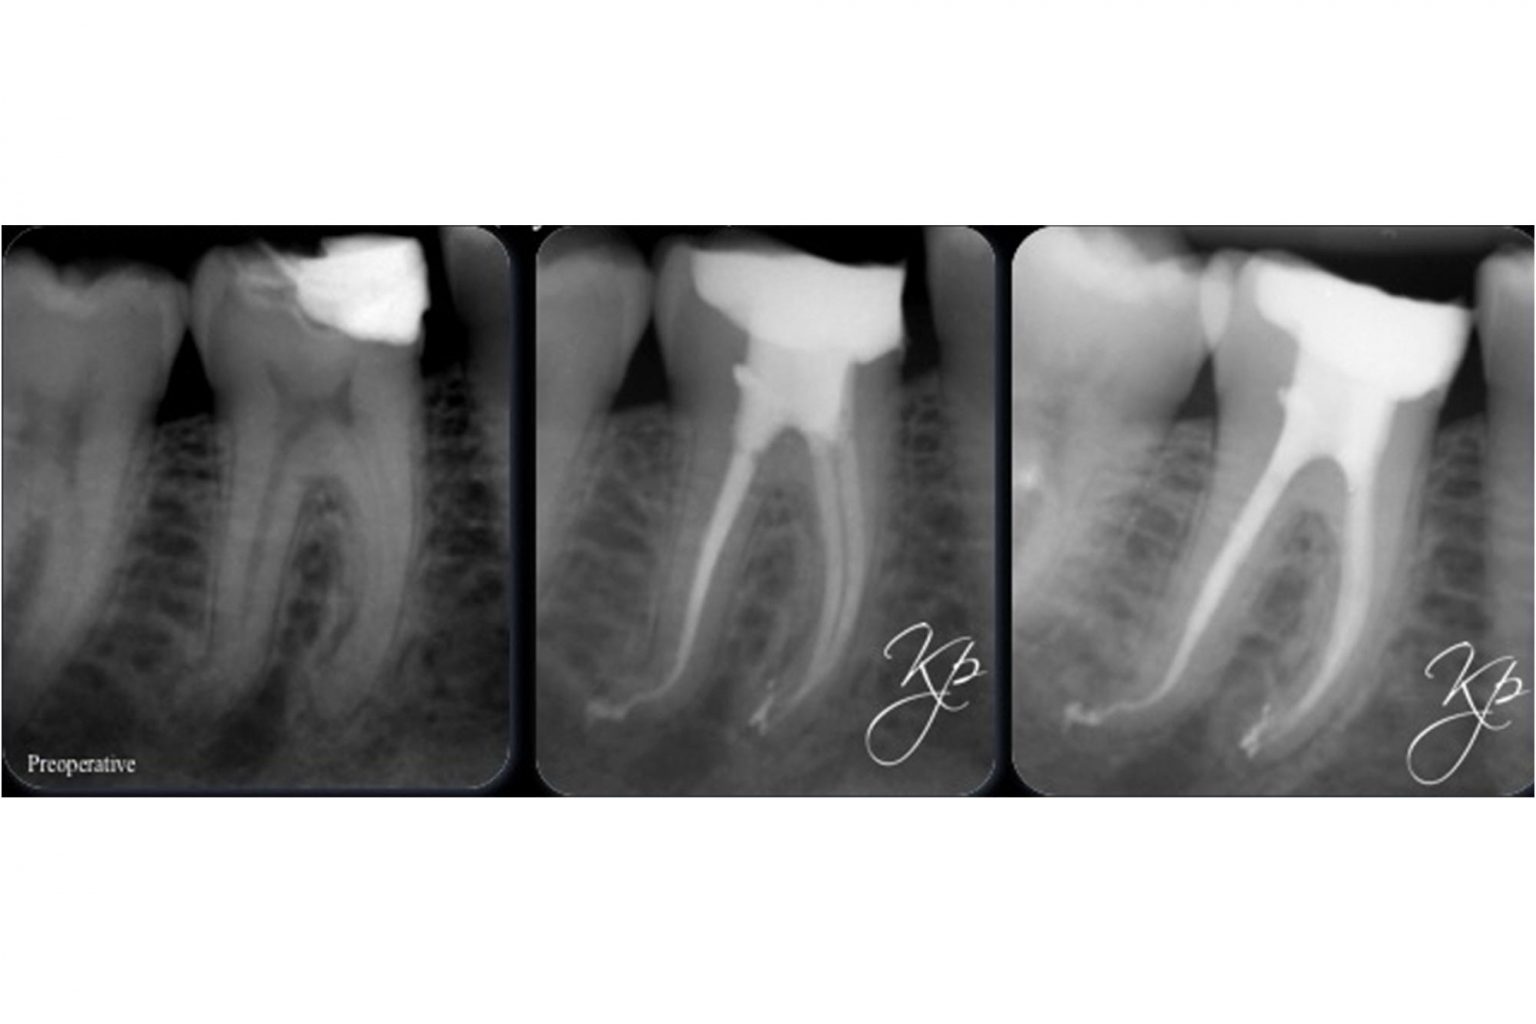

The endo expert managing curved canals Dentistry Online

The endo expert managing curved canals Dentistry Online Curved Tooth Root X-Ray Dilaceration is a developmental disturbance in shape of teeth. This systematic review presents an overview of the published techniques for the. This month kreena patel explores how to manage curved canals during endodontic treatment. The assessment of root canal curvature is essential for clinical and research purposes. This systematic review presents an overview of the. It refers to an angulation,. Curved Tooth Root X-Ray.